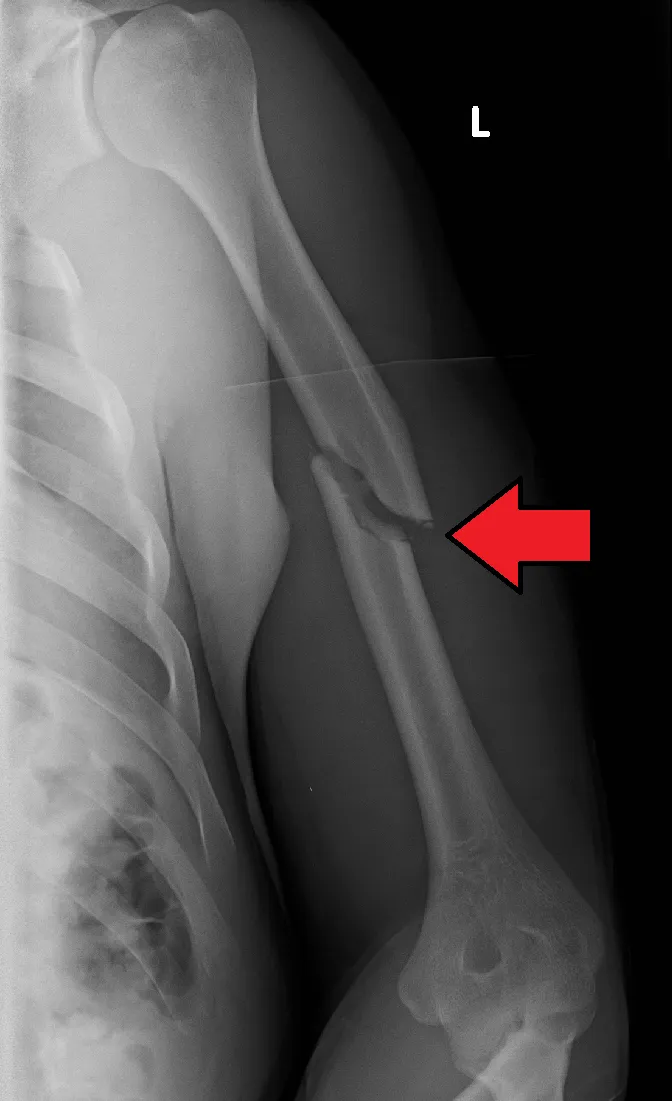

Röntgenfoto: met een röntgenfoto van de bovenarm (inclusief schouder en elleboog) bevestigt men de breuk en bekijkt men de positie van de botstukken. Soms zijn opnamen in meerdere richtingen nodig om de breuk volledig te beoordelen.

Een gebroken bovernarm (humerusfractuur) is een botbreuk van het bovenarmbot (humerus). Dit kan zich voordoen in het middelste deel van het bot (schacht) of dichter bij de schouder of elleboog. Een humerusfractuur ontstaat meestal door direct trauma (zoals een harde val of een verkeersongeval) of een krachtige draaibeweging van de arm (soms bij armworstelen). Soms breekt het bot op meerdere plaatsen of steekt een botpunt scherp onder de huid (open fractuur).